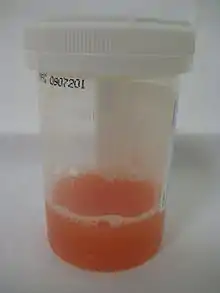

| Type | WBC (per mm3) | % neutrophils | Viscosity | Appearance |

|---|---|---|---|---|

| Normal | <200 | 0 | High | Transparent |

| Osteoarthritis | <5000 | <25 | High | Clear yellow |

| Trauma | <10,000 | <50 | Variable | Bloody |

| Inflammatory | 2,000–50,000 | 50–80 | Low | Cloudy yellow |

| Septic arthritis | >50,000 | >75 | Low | Cloudy yellow |

| Gonorrhea | ~10,000 | 60 | Low | Cloudy yellow |

| Tuberculosis | ~20,000 | 70 | Low | Cloudy yellow |

| Inflammatory: Arthritis, gout, rheumatoid arthritis, rheumatic fever | ||||